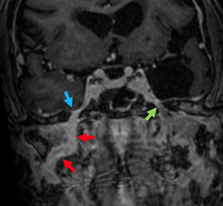

The imaging workup included MRI of the paranasal sinuses and brain, which showed a lesion in the right cavernous sinus with enhancement in the path of the right maxillary (V2), vidian, and mandibular (V3) nerves, consistent with perineural tumor spread (Figure 1) (Figure 2).

Figure 1 Magnetic resonance imaging, T1-weighted sequence with fat suppression. Coronal slices showing anomalous contrast enhancement in the foramen rotundum (red arrow) and pterygoid canal (blue arrow).

Figure 2 Magnetic resonance imaging, T1-weighted sequence with fat suppression. Axial slices showing anomalous contrast enhancement in the right foramen rotundum (red arrow), normal on the left (green).

Transnasal endoscopic surgery was performed to attempt biopsy of the cranial nerves with suspected involvement. Complete resection of the lesion was ruled out due to involvement of the cavernous sinus and because there was no histopathological diagnostic confirmation. Initially, a maxillary antrostomy was performed, followed by a post-lacrimal maxillectomy for expanded access to the floor and medial wall of the nasal cavity. The posterior wall of the maxillary sinus was then removed to expose the pterygopalatine fossa. An incisional biopsy was performed in the neurovascular structures covering the palatine bone, with the infraorbital nerve as the lateral limit. Then, the sphenoid sinus was opened and dissected down to the floor, exposing the vidian nerve (Figures 3A and 3B). On the lateral wall, the foramen rotundum was opened to expose CN V2 (Figures 3C and 3D). All specimens were sent for frozen sections, which revealed carcinomatous infiltration of nerve fibers, conclusively demonstrating perineural tumor spread. Postoperative treatment consisted of radiation therapy alone.

Figure 3 Transnasal exposure (zero-degree endoscope) of pterygopalatine fossa and sphenoid sinus on the right. A: Identification of the foramen rotundum and pterygoid foramen after partial resection of the structures of the pterygopalatine fossa; B: vidian nerve resection; C and D: opening of the foramen rotundum and exposure and undermining of the maxillary nerve up to the cavernous sinus.